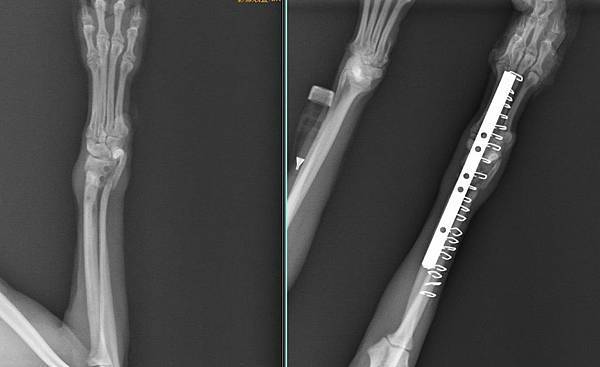

骨折不癒合 自體骨移植

荳荳已經骨折一個月了

有在持續治療但都沒有長骨頭

所以跑來找小譚醫師想辦法

經過醫療團隊進行

自體骨移植手術後

一周已經能自行走路了